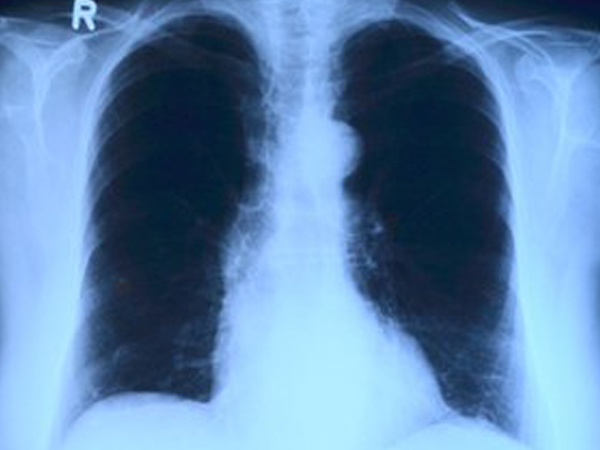

நுரையீரலில் நீர் தேக்கம் என்பது பல்வேறு உடல் உபாதைகளுக்கான அறிகுறியாக இருக்க முடியும். நிமொனியாவின் சில வடிவங்களுக்கு இது ஒரு பொதுவான அறிகுறியாகப் பார்க்கப்படுகிறது. ஆனால் நுரையீரல் புற்றுநோய் காரணமாகவும் இந்த நீர் தேக்கம் ஏற்படலாம்.

அல்லது மிகவும் அரிதாக இடைத்தோலியப் புற்று நோய் எனப்படும் மெசொதேலியோமாவின் காரணமாக இருக்க முடியும். அதனால் நுரையீரலில் நீர் தேக்கம் உள்ளதற்கான அறிகுறிகள் தென்பட்டால், உடனடியாக மருத்துவ ஆலோசனைப் பெறுவது நல்லது.

பெரும்பாலும் ஒரு எக்ஸ்ரே அல்லது EKG எடுத்துப் பார்த்து, எந்த இடத்தில் திரவம் சேர்ந்துள்ளது என்பது பரிசோதனையில் கண்டறியப்படும். இதன் மூலமாக, முன்கூட்டியே நுரையீரல் புற்றுநோய் ஏற்படக் கூடிய வாய்ப்பு களையப்படும்.